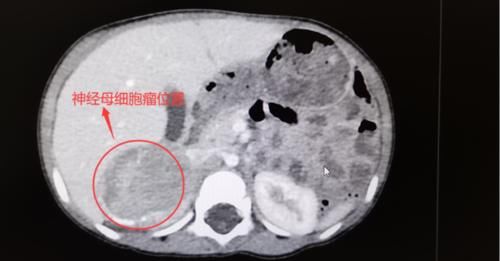

湖南长沙的张女士自从女儿澜澜出生后,就辞职在家细心照顾孩子,但是没想到今年1岁7个月的澜澜在一次常规的体检检查,竟然在左侧腹腔深处,靠近脊柱部位查出身体里长了一个巨大肿瘤。

孩子妈妈瞬间懵了,急得像热锅上的蚂蚁,经过湖南妇女儿童医院儿保科谭传梅主任的详细检查,联合多名专家进行紧急会诊,这个突如其来的“巨瘤”被诊断为神经母细胞瘤,澜澜马上就被安排住院进行手术,经过治疗最终转危为安健康出院。

神经母细胞瘤是一种儿童常见的实质性肿瘤,婴幼儿至5岁是高发年龄,约75%患者在5岁以下。

大约65%的肿瘤起源于腹部,15%-20%起源于胸部,其余15%起源于不同的部位例如颈部、骨盆等。

神经母细胞瘤年龄越小,发现越早,越容易治愈,晚期大年龄患儿的长期无病生存率仅为5%-30%。